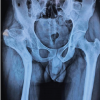

The systematic review included a total of 30 RCTs that met all eligibility criteria and provided detailed data on the use of PRP for treating rotator cuff tendinopathy. These studies represented a broad range of patient populations, PRP preparation techniques, and control interventions, each contributing unique insights into the efficacy of PRP in this context. Fig. 1 highlights the PRISMA flow diagram illustrating the selection process of studies included in the systematic review and meta-analysis.